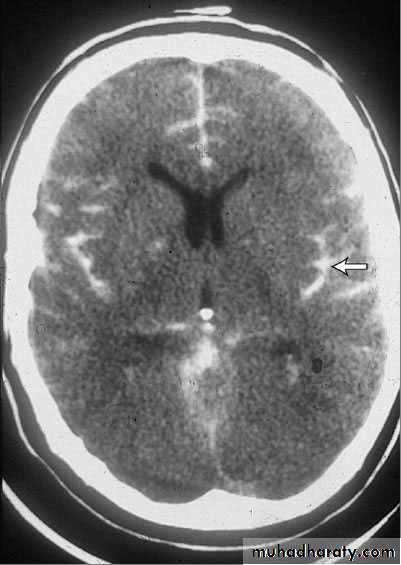

Usually noncontrast CT and, if negative, lumbar puncture

Noncontrast CT is > 90% sensitive and is particularly sensitive if it is done within 6 h of symptom onset. MRI is comparably sensitive but less likely to be immediately available. False-negative results occur if volume of blood is small or if the patient is so anemic that blood is isodense with brain tissue. If subarachnoid hemorrhage is suspected clinically but not identified by neuroimaging or if neuroimaging is not immediately available, lumbar puncture is done .